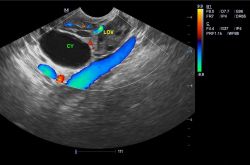

- 卵巢囊肿怎么治疗最好方法?卵巢囊肿的症状

卵巢囊肿是发生在女性身上的一种疾病症状,其生长在卵巢内的一个像肿瘤一样的小包,里面有着液体,但是并不会对身体有一个的健康影响,那囊肿是怎么形成的呢,出现这...

- 卵巢疾病分类有哪些 卵巢囊肿的症状是什么

卵巢是女性孕育下一代的主要的生殖器官,与女性的青春也密切相关。一旦发生异常病变的话,往往会用影响到女性的生殖功能和内分泌平衡。那么,卵巢疾病分类有哪些?卵巢囊肿的症状是什么呢?下面不妨跟随东方女性网小编一起了解相关知识......